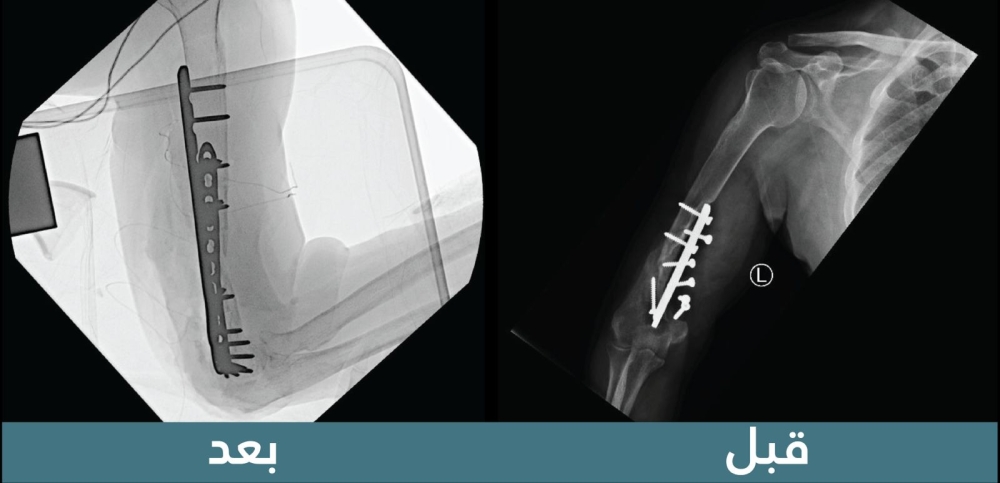

أنهت مدينة الملك سعود الطبية، عضو تجمع الرياض الصحي الأول، معاناة مريض في العقد الخامس من عمره عانى لمدة 19 عامًا من فقدان الحركة في مفصل الكوع الأيمن، مصحوبة بآلام مزمنة.

قامت المدينة بتشكيل فريق طبي متخصص في قسم جراحة العظام، بقيادة الدكتور بندر السهلي والدكتور حسين الياسين، حيث أجروا الفحوصات اللازمة التي كشفت عن إصابة شديدة في العضد الأيمن، بالإضافة إلى الالتهابات وعدم التئام في العظم ونخر عظمي شديد.

استنادًا إلى النتائج، تم تجهيز عظم تعويضي وشرائح متخصصة لإجراء عملية جراحية دقيقة تهدف إلى ترميم الجزء العظمي غير الملتئم وتحرير المفصل. تكللت العملية بالنجاح ولله الحمد، حيث تمكن المريض من استعادة حركته والعودة إلى حياته اليومية بشكل طبيعي.